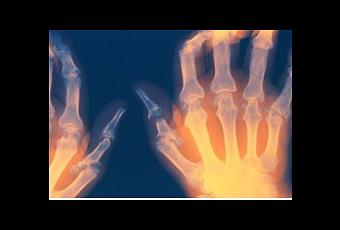

Cette recherche présente un potentiel important pour la prise en charge de la douleur chronique et de la douleur neuropathique à des lésions aux nerfs eux-mêmes. Les chercheurs expliquent que la fréquence avec laquelle les nerfs impliqués dans la détection des signaux de douleur envoient des signaux au cerveau affecte la sensation de douleur. Cette fréquence pourrait être influencée par les canaux ioniques, dont ceux de la famille HCN, à laquelle appartiennent les gènes HCN1 et HCN2. Ces gènes sont présents à des niveaux élevés dans les nerfs impliqués dans la douleur et les sensations comme le toucher. De précédentes expériences ont suggéré que HCN1 ne joue pas un rôle important dans la sensation de douleur, les chercheurs ont donc étudié le cas de HCN2.

La présence du gène HCN2 est donc nécessaire pour la détection des douleurs neuropathiques. Les prochaines étapes seraient de réussir à bloquer sélectivement l'action de HCN2 et de pouvoir développer ensuite, sur ce principe des médicaments contre la douleur pour bloquer les effets de la douleur neuropathique et inflammatoire.